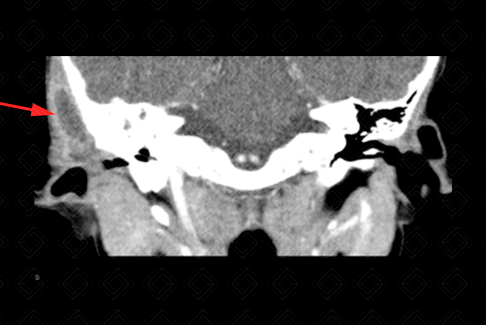

Descrição das figuras: Tomografia computadorizada das mastoides com contraste venoso. Observa-se no plano axial com filtro ósseo o preenchimento das células mastoideas à direita. As células mastoideas à esquerda encontram-se normoaeradas. Há ainda presença de coleção no ouvido externo à direita (setas vermelhas). Os planos axial e coronal caracterizam um quadro de otomastoidite à direita.

Mastoidite aguda: Trata-se da infecção das células mastoideas, representando a complicação mais comum das otites. Deve ser realizada com contraste venoso, para afastar possíveis complicações como coleções, trombose de seios venosos, erosões ósseas, osteomielites de base do crânio, abscessos cerebrais, meningite e outras

• Tomografia computadorizada das mastoides: O bserva-se preenchimento das células mastoides, com erosão dos septos. Deve ser realizada após a administração do contraste venoso para afastar complicações, como coleções, trombose de seios durais, abscessos cerebrais, osteomielite, erosões ósseas e outros;